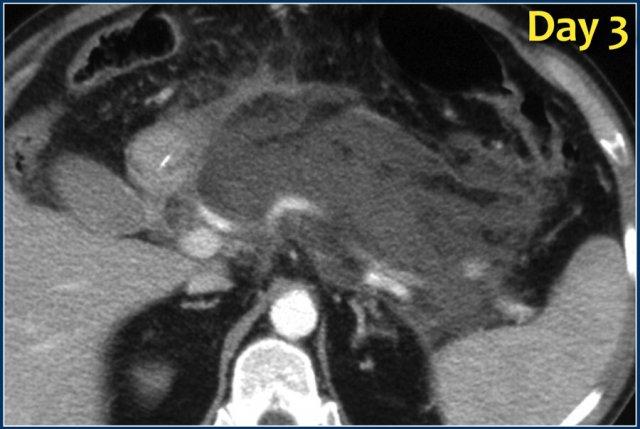

Các hình ảnh cho thấy tụy ngấm thuốc bình thường vào ngày thứ 1.

Khi tình trạng bệnh nhân xấu đi, CT lần hai được thực hiện vào ngày thứ 3.

Lưu ý phần lớn thân và đuôi tụy không còn ngấm thuốc, gợi ý viêm tụy hoại tử (các mũi tên).

CT lần đầu đã đánh giá thấp mức độ nặng của viêm tụy.

Bệnh nhân này tử vong vào ngày thứ 5 do hội chứng đáp ứng viêm hệ thống (SIRS) nặng và suy đa tạng.